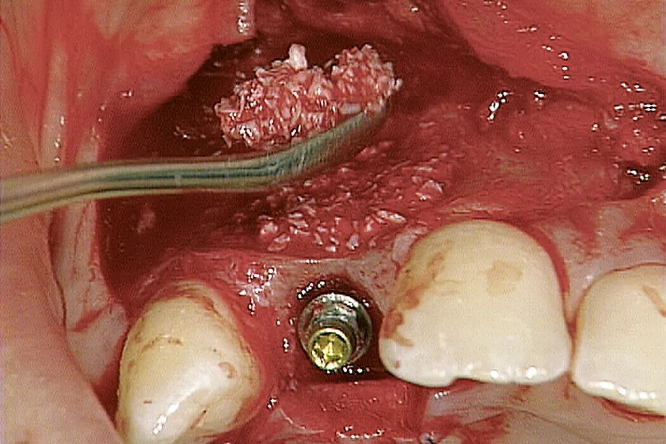

图片左侧: Geistlich Bio-Oss® 与人体骨非常相似(放大倍数50倍)。图片右侧: 人体骨的独特结构 (放大倍数50倍)。 Geistlich Bio-Oss® 颗粒的超级多孔结构有助于新骨形成。(放大倍数:5000倍) 术后9年:新骨直接接触Geistlich Bio-Oss® 颗粒。骨在骨小梁结构与Geistlich Bio-Oss® 之间、无机骨基质之间形成桥梁结构。 Geistlich Bio-Oss® 的成骨效果好,提升种植体存活率4,5 Geistlich Bio-Oss® 方便操作,且临床适应症非常广泛 Geistlich Bio-Oss® 已经在临床领域成功应用了25年,目前有超过700篇科学研究文献 “ 盖氏产品多年以来深得我信赖。” PROF. MARIANO SANZ, 西班牙马德里 十九世纪八十年代,Dr. Peter Geistlich突破性地将有机成分从骨材料中除掉,而又不破坏其自然微观结构和骨组成。如今,Geistlich Bio-Oss® 已经被认为是口腔骨再生领域中先进的骨替代材料——满足临床医生对预期疗效的需求。 Geistlich Bio-Oss® 操作简单 Geistlich Bio-Oss® 具有良好的易操作性及始终如一的临床优异表现。 使用前,将Geistlich Bio-Oss® 和血液或生理盐水混合。它的亲水性促进迅速、彻底的水合。 Geistlich Bio-Oss® 易于构建成骨空间,并黏附于骨壁缺损处。 切勿过度挤压,要为新骨形成留出足够的空间。 配合胶原膜使用,如Geistlich Bio-Gide® ,能获得更好的骨再生疗效。 在容器中将Geistlich Bio-Oss® 与缺损区渗出血液或生理盐水混合。颗粒间具有很好的粘附性。 Geistlich Bio-Oss® 易成型,为给新骨生成留出空间,不需要用力按压。 在植骨区上覆盖Geistlich Bio-Gide® ,以确保新骨生成不受干扰。 Geistlich Bio-Oss® 大小颗粒共有五种规格适用于骨缺损。 可以很好地覆盖周围的表面轮廓。 特别适用于小面积缺损和自体骨移植的轮廓填充。 有以下规格: 0.25 g ~ 0.5 cc 0.5 g ~ 1 cc 2 g ~ 4 cc